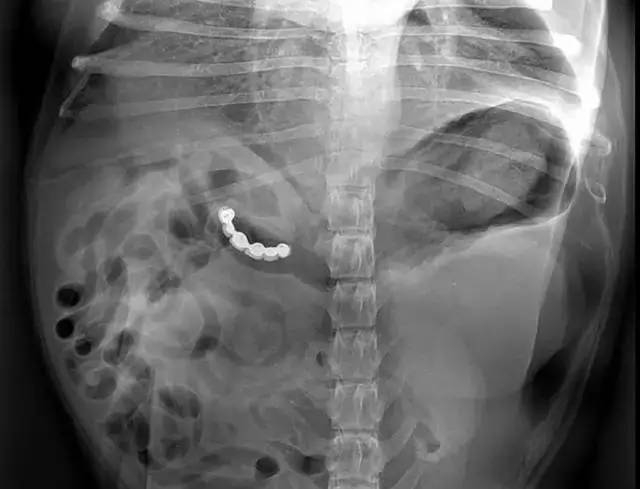

江苏3岁孩子玩耍时吞了13颗磁珠,竟然造成肠子上11个穿孔!通过手术取出了13颗磁珠。

医生手术中还发现孩子肠管共有11个穿孔,穿孔处已经有些坏死发暗。医生切除坏死的肠管后,重新缝合。13颗磁珠取出后,有几颗已经有些腐蚀变黑了。